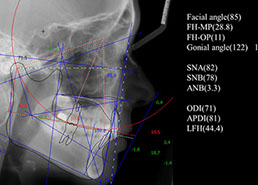

すべての治療において何よりも大事なのは診断であり、矯正治療においてもそれは変わりません。 診断とは、現在の状態を把握するための病態診断と、再発防止のための発症メカニズムの診断、そして具体的な治療目標 end point 決定のための診断から成り立ちます。 当院ではこれらの診断のため、インビザライン治療においても、いろいろな事前検査をしていることが、当院でのインビザライン治療の特徴であるとともに、患者さんにとっての最大のメリットにつながると信じています。 経歴 1989年 埼玉県立春日部高校卒業 1993年 埼玉大学理学部卒業 2002年 日本歯科大学を首席で卒業 2014年 銀座ルミナス歯科開設

精密検査 (来院)¥60,000(税抜) 2回のカウンセリング後、治療を希望される場合には、治療計画を立てるために必要な精密検査を受けていただきます。 CADIAXという検査機器による下顎運動の測定やセファロレントゲン撮影などの画像検査が含まれます。 カウンセリング 3回目 (来院またはオンライン) 無料/60分 精密検査から診断がなされ、診断に基づいた治療計画を立案します。治療計画はアライン・テクノロジー社が開発した3D治療計画ソフトウェア「クリンチェック」を使います。 3D治療計画では、予測される最終的な歯並び(治療結果の保証ではありません)が示されるほか、おおよその治療期間も提示されます。 3回のカウンセリングにより、歯科医師が考えるゴールと患者さんの考えるゴールについてのすり合わせを行い治療方法を決定します。